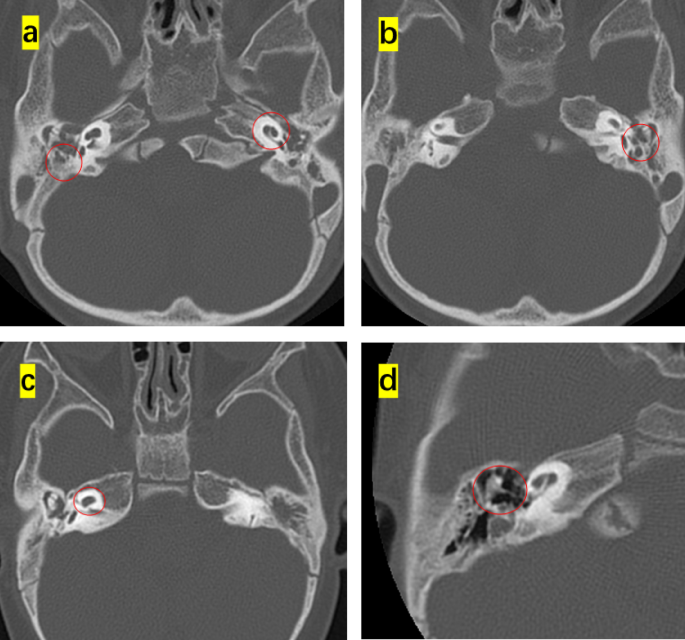

This study enrolled 16 children (8 months to 4 years old) that were diagnosed with diverse phenotypes of syndromic hearing loss and underwent CI. These included six, three, one, and six cases of WS, NS, KS, and CS, respectively. Children with different types of NCP-based hearing loss exhibit unique facial features: the iris of children with WS were heterochromic, and there were no abnormalities in the head and facial structure; the patients with NS had protruding foreheads, widened eye distances, and downward inclination of the eye fissures; the patient with KS had cracks on the long eyelid, with a slight outward rotation of one-third of the lower eyelid and a cup-shaped ear on the right side; all the CS patient were with predominant craniofacial anomalies involving the ears and eyes. Table 1 shows the main clinical features of the 16 children, specifically highlighting the ear malformations and the degree of developmental delay. There were observable differences between the types of syndromic hearing loss. WS and NS showed mild malformations of the middle and inner ear (Figs. 1 and 2). KS (Fig. 3) primarily exhibited malformations of the outer and middle ear structures. CS (Fig. 4) showed significant malformations in the outer, middle, and inner ear and showed varying degrees of stenosis or occlusion of the cochlea in different cases (Fig. 5). Cochlear nerve canal stenosis was observed in almost every CS case. Apart from WS, the other three syndromes showed clear craniofacial malformations, growth delay, and varying degrees of neurodevelopmental delay. Gesell scores were below the normal value of 85. Among the syndromes, WS and NS exhibited mild symptoms, KS showed more pronounced symptoms, and CS cases were the most severe.

Ear CT scans in CHARGE syndrome(CS) cases. (a-c) Developmental abnormalities in the middle and inner ear of CS, including underdeveloped semicircular canals, vestibular malformations, an abnormal facial nerve course, a narrow internal auditory canal, and cochlear apical–middle turn hypoplasia. (d) Ossicular chain abnormalities.